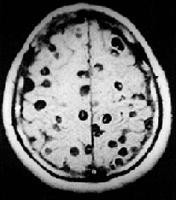

+Chụp cắt lớp vi tính (CT Scanner) não tìm các hình ảnh đặc hiệu (các nang sán là những nốt dịch có chấm mờ, kích thước 3-5mm, đôi khi nang có kích thước lớn đến 10mm, rải rác có nốt dạng vôi hóa);